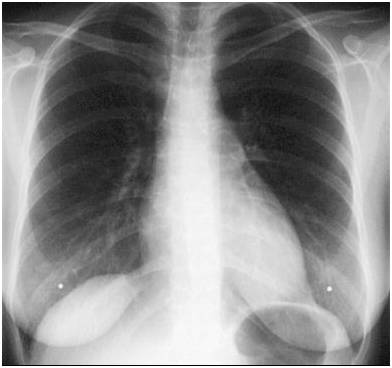

小编每次会放一张正常胸片对比:

胸片显示:两肺多发的大小不等的结节影,形如棉花团。

病理结果:宫颈癌肺转移。

4、最重要的X线表现:X线一般特点为两肺多发结节影,肺尖部稀少,两肺中、下野外带分布较多,晚期部分病灶可融合。大的像棉花团,小的像粟粒状,就是小米粒样。边缘光滑,多无分叶或毛刺。密度较淡,质地均匀。